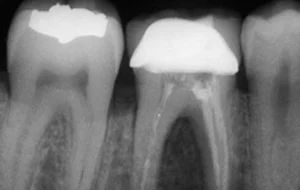

• The very first step involves an X-ray which is taken to determine the extent and approach to infection. If required local anesthesia is administered before starting the treatment.

• The next step is Cavity Preparation. A cavity is prepared, making sure all the infected tooth material or previous filling material is removed and a proper approach to inner-part of the tooth (pulp) is established.

• This is followed by disinfection and shaping of pulp canals. The infected pulp is cleared out completely, canals are shaped and cleaned. Thorough disinfection is achieved.

• Clean and disinfected canals are then sealed and filled with an inert rubber-like filling material known as Gutta-Percha.

• The very last step is restoration & crown. The crown portion of the tooth cavity is then restored with a filling, followed by a Cap/Crown cementation.